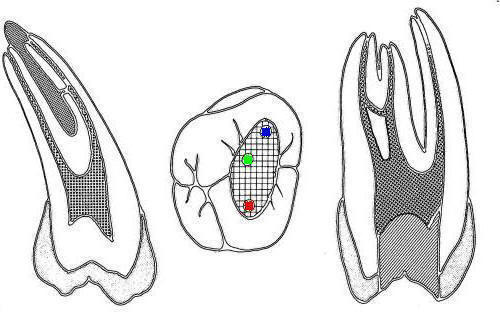

• En azul conducto mesio-vetibular

• En verde conducto mesio-lingual

• En rojo conducto distal

• En amarillo un cuarto conducto,  si el conducto distal se encuentra desplazado hacia lingual, existe una alta posibilidad de encontrar un cuarto conducto

Tres conductos en piso de cámara pulpar, el conducto distal se encuentra ensanchado en sentido buco-lingual, debe sospechar la existencia de dos conductos que comparten el orificio de entrada. Cámara intraoral X10 aumentos.